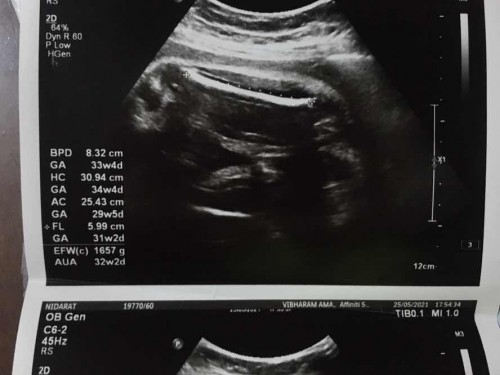

พอดีไปตรวจครรภ์ล่าสุดมา หมอบอกว่าอายุครรภ์ประมาณ 33 weeks แต่น้องหนักแค่ 1676 กรัมเองคะ ทำไงดีคะ น้ำหนักน้อยไปมั้ย ต้องกินอะไรให้ลงน้องเยอะๆ